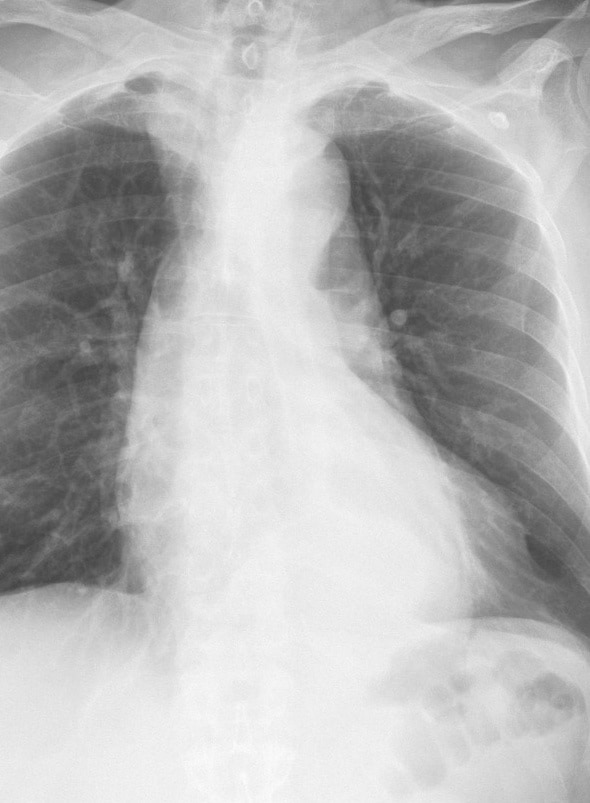

Bóc tách ĐM chủ ngực

» Thông tin: Nam giới – 72 tuổi.

» Lâm sàng: Đau ngực.